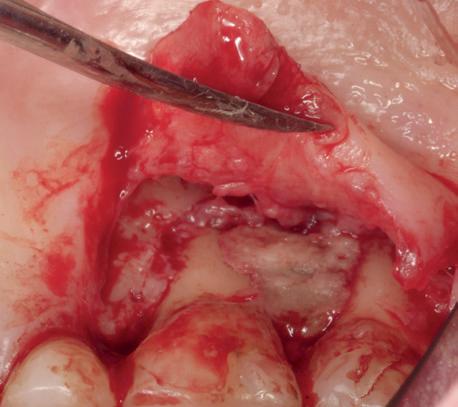

In deze casus is extractie van de 37 geïndiceerd in verband met een fistel en restpockets, zoals zichtbaar op de röntgenfoto’s (afbeelding 1). Duidelijk te zien is de forse peri-apicale ontsteking en het botverlies bij de 37, dat zowel richting buccaal als linguaal doorloopt. De 37 wordt atraumatisch verwijderd. Er is aan de linguale zijde veel bot verloren en er is sprake van een perforatie aan de buccale zijde.

Er wordt besloten om botmateriaal te plaatsen in de extractie-alveole. Vervolgens wordt het afgesloten met een titanium versterkt d-PTFE membraan (afbeelding 2). Na vier weken wordt het membraan verwijderd.